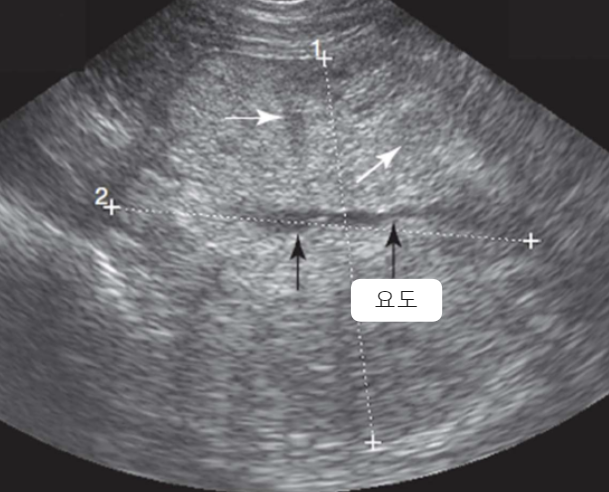

| Ultrasonography (Abd) | _Pyelonephritis |

|---|---|

| - 대표적으로 일시적인 콩팥 비대 (renal pelvic dilation) - Ureteral dilation (요관 확장) - Blunting of the renal papilla (콩팥유두의 둔화) - Echogenic debris (내부에 고에코성 잔해) * 신우신염인데 콩팥이 축소되어 있으면, CKD나 만성 신우신염을 의심해보자. + Bacterial culture : pyelocentesis(신우천자)는 실질을 건드릴 수 있으니, 방광 sampling부터 시도 |